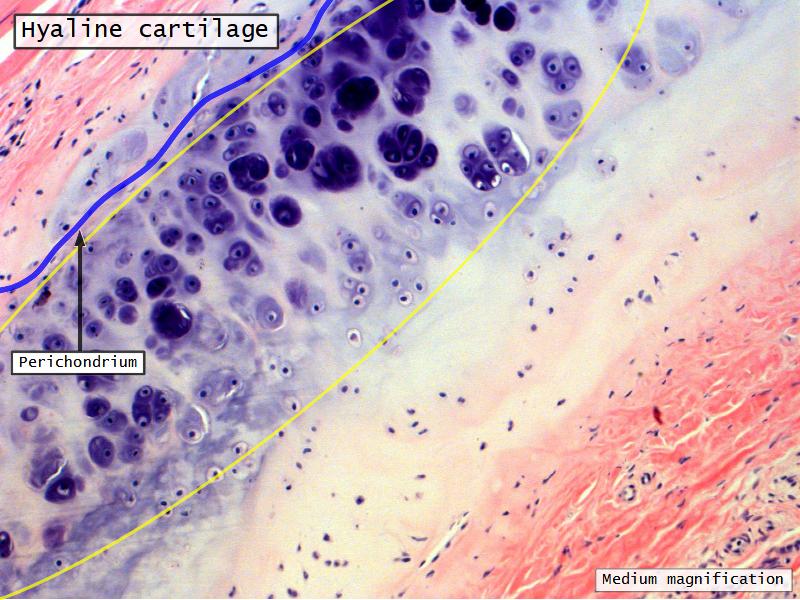

Epiglottis